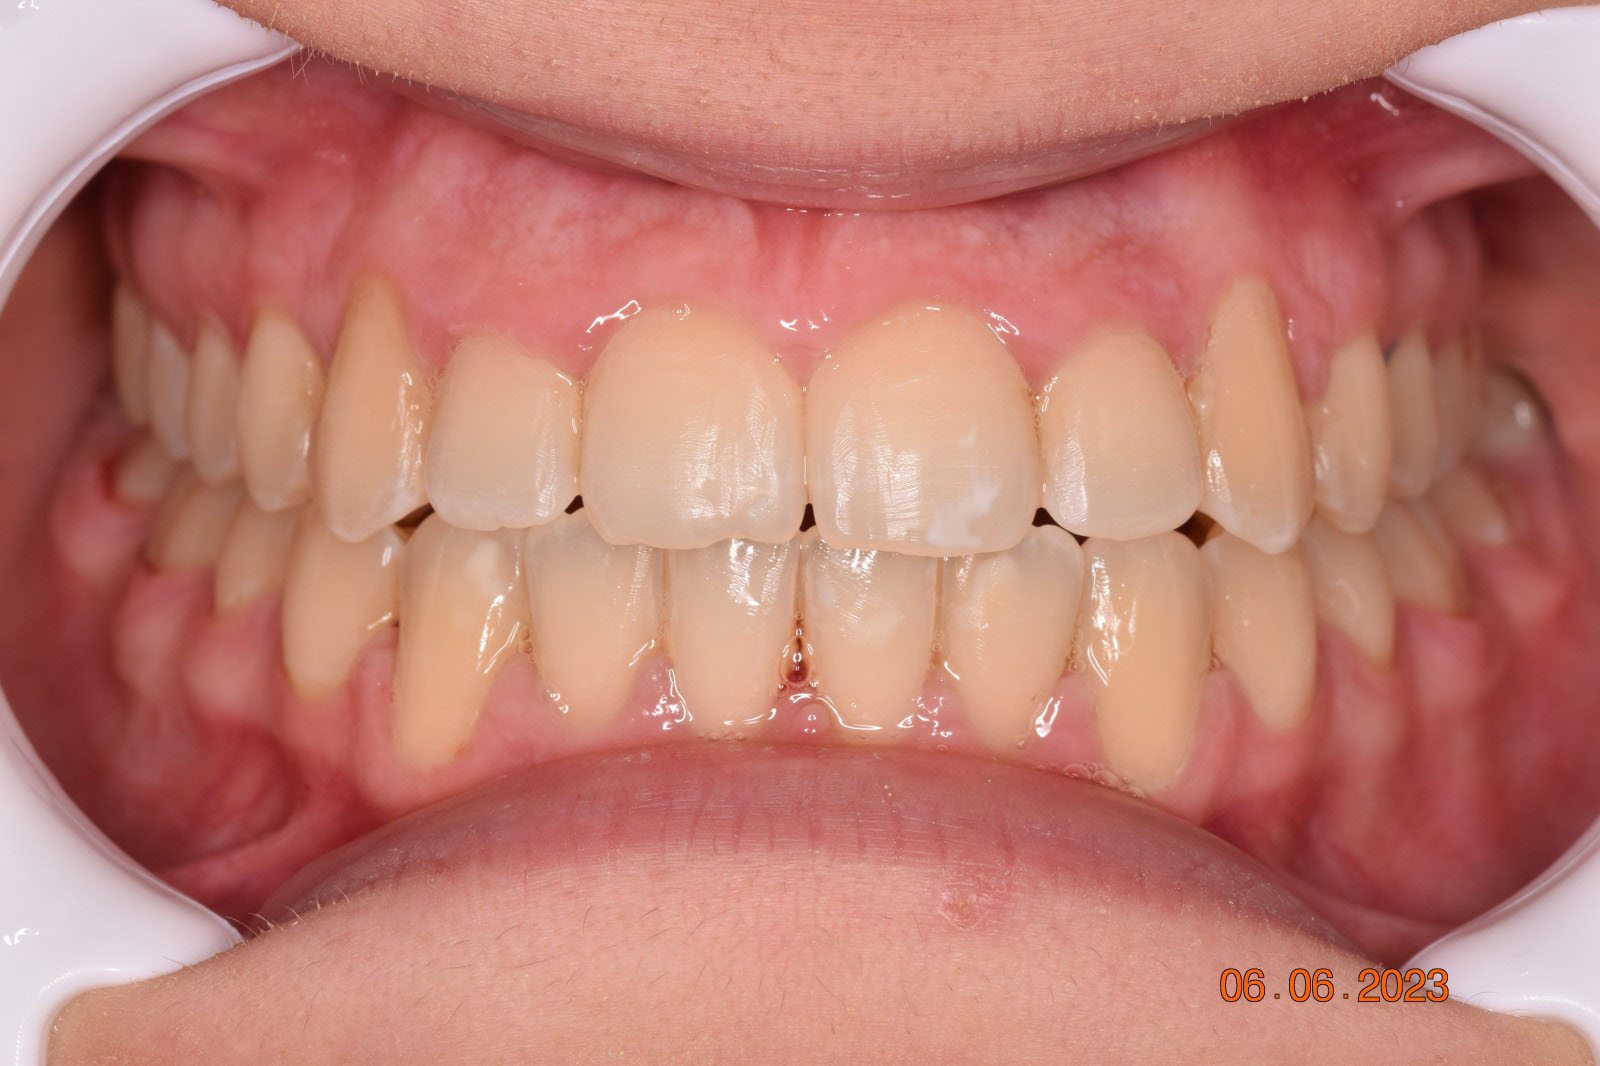

The teeth are in a very good position and the bone has reshaped.

This case posed challenges in all three spatial dimensions, compounded by significant crowding. The patient was highly compliant and maintained excellent oral hygiene throughout the 5.5 years of treatment, which required more than 30 clinical appointments.

The facial changes are impressive considering treatment involved only conventional orthodontics and not orthopedic interventions, TADs, or surgery.

Dr. Coca concludes that improved biomechanical understanding of extreme crowding and torque management could have reduced treatment duration. From his experience, proper force management can facilitate bone remodeling, challenging the idea of bone limitations in orthodontics.

Correcting muscle behavior during swallowing and in the passive state is key to solving open bite and crossbite as well as ensuring lasting stability of treatment outcomes.

Dr. Coca believes that with his current experience and insights, he could have completed the case within three years.

This case was a learning moment for Dr. Coca, reshaping his understanding of low-force, low-friction orthodontics (also known as Damon Philosophy) and highlighting the power of myofunctional therapy in achieving optimal treatment outcomes.